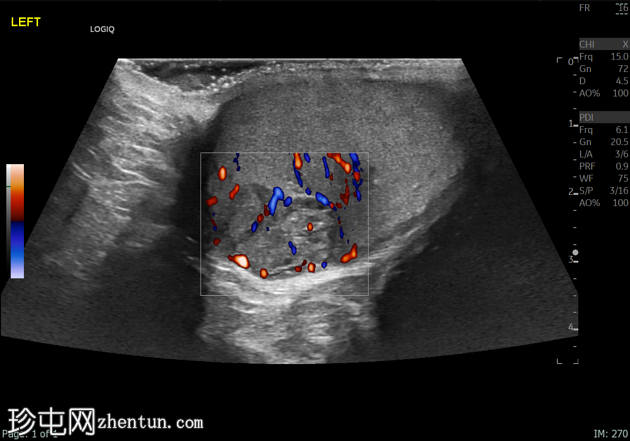

超声检查

左侧睾丸肿大,体积约56 mL,可见弥漫性微结石,以及三个内部等回声病灶,伴囊性变、微钙化和明显血流信号,最大病灶大小约4.8 x 3.2 cm。

未见腹主动脉旁或髂淋巴结肿大。